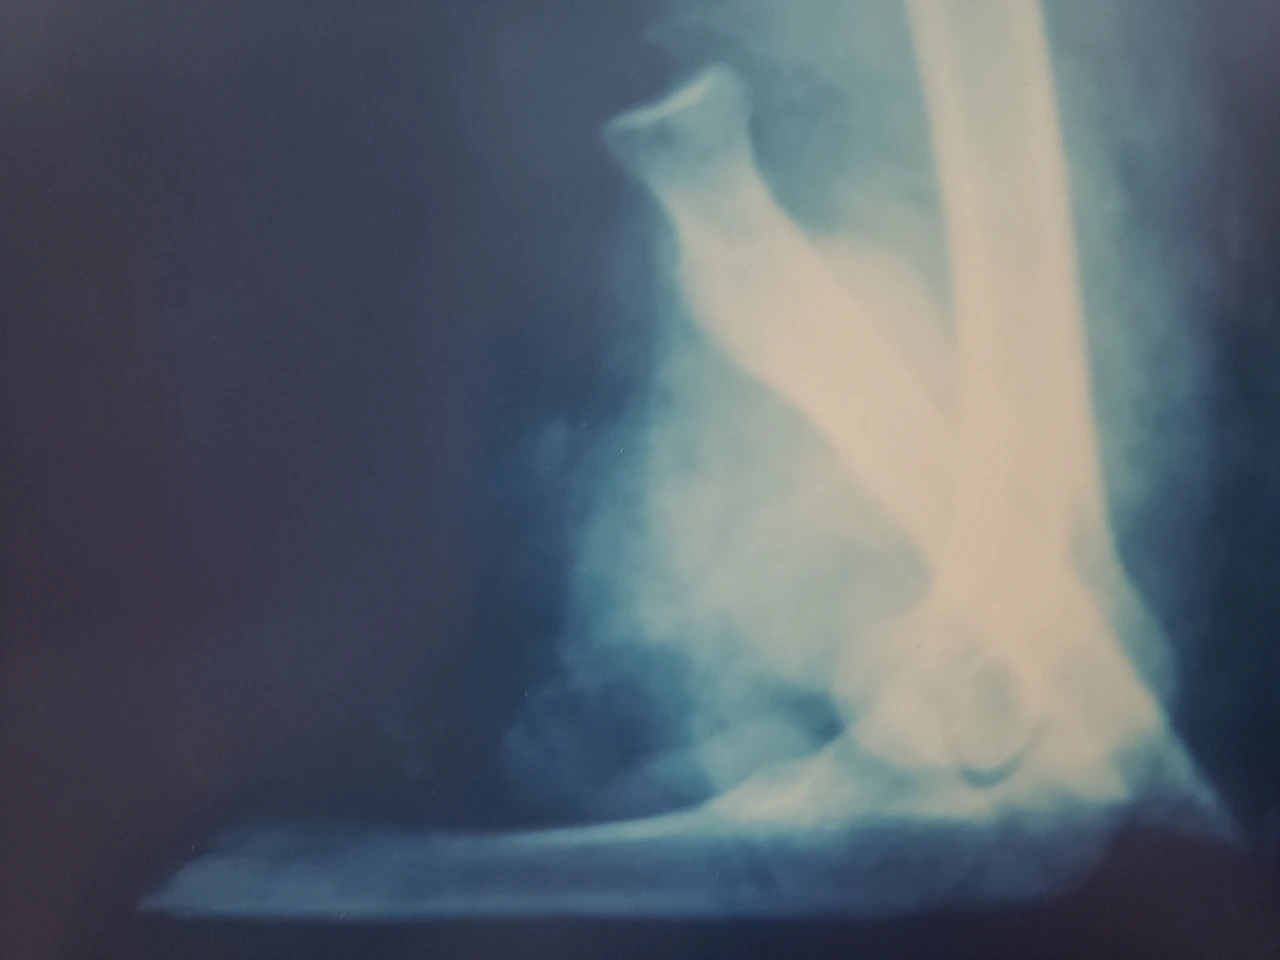

당직 콜은 받은 나는 환자와 절단된 팔과 엑스선 필름을 찬찬히 훑어보았다.

35세의 남자 환자로 타이어 공장에서 새벽 근무를 하다 졸음을 이기지 못하고 그의 오른 팔이 기계 롤러 사이에 끼어들어가 끊어지고 말았다. 절단되었다기보다는 팔이 뽑혀나갔다고 하는 것이 맞다고 할 정도로 근육과 신경, 혈관들이 엉망이었다. 그러나 신기하게도 손 부위와 손목, 팔 부분은 포기하기 아까울 정도로 깨끗하여 재접합을 염두에 두고 곰곰이 생각해 보았다.

그리고 천천히 골절 부위를 관찰하였다. 팔에는 뼈가 두 개인데 요골과 척골이라고 한다. 요골의 윗부분은 손을 회전하는데 쓰이는데 이 경우는 팔을 구부리는 것으로 만족하여야 할 상황이라 비틀린 요골의 윗부분은 제거하였다. 척골의 절단면을 찾아 호프만이라는 외고정 기기로 우선 골 접합을 마무리하였다.